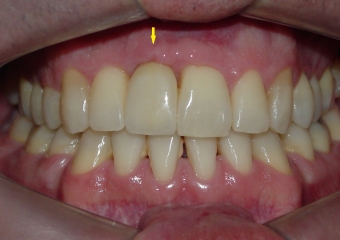

Imagem inicial